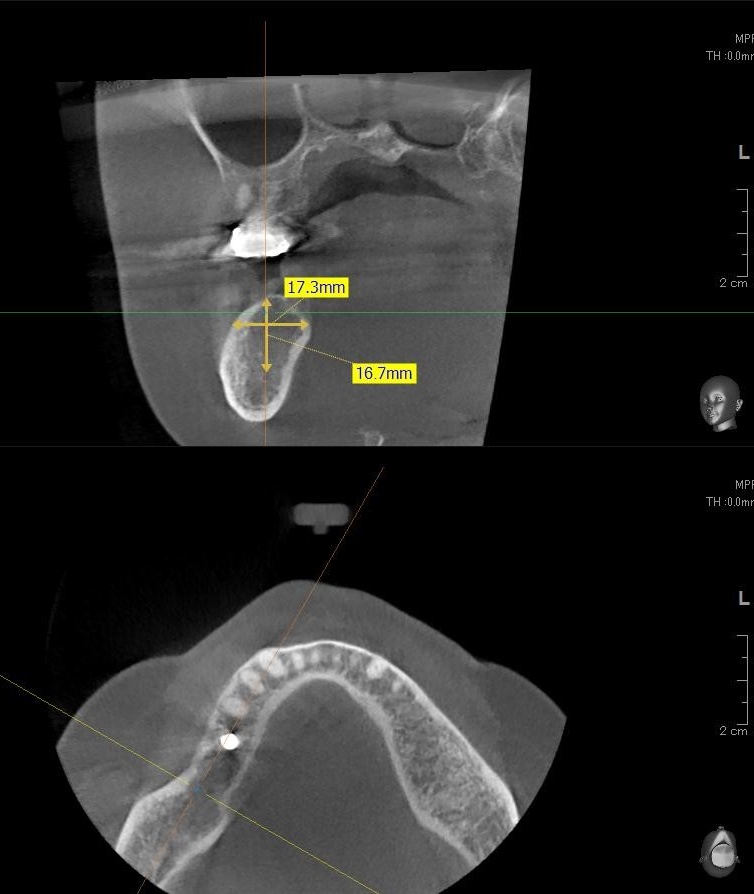

今回の患者様はインプラント植立を希望され、右下6番目・7番目の2本の植立が決まりました。

ドリルの先端を細い物から徐々に大きい物に変えながら、植立するインプラント体のネジの部分を除いた胴の部分の太さに合わせた大きさの穴を開けていきます。

開けた穴に、専用道具を使ってネジを締めるように長さ2センチ程のインプラントを骨に埋め込んでいきます。